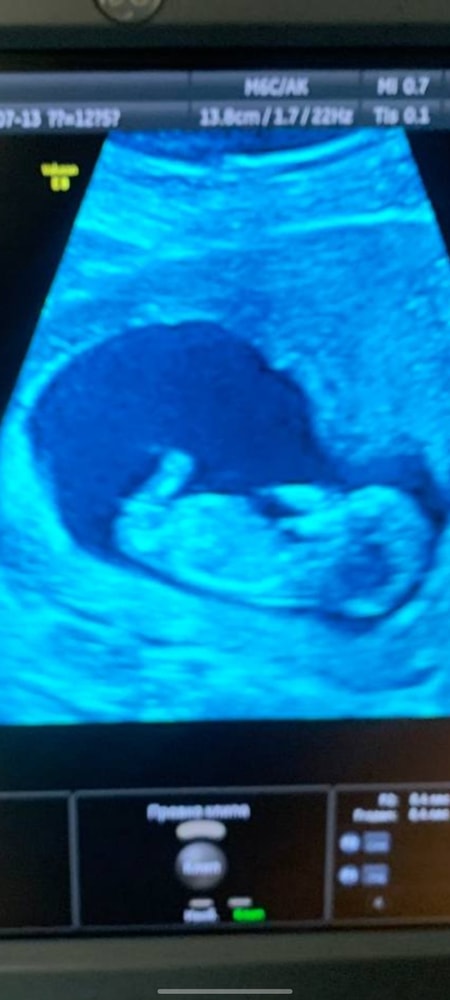

Девочки подскажите на кого похожа , как думаете , мальчик девочка?

Как думаете кто ? Девочка мальчик , погадаем )))

На ребенка 💯